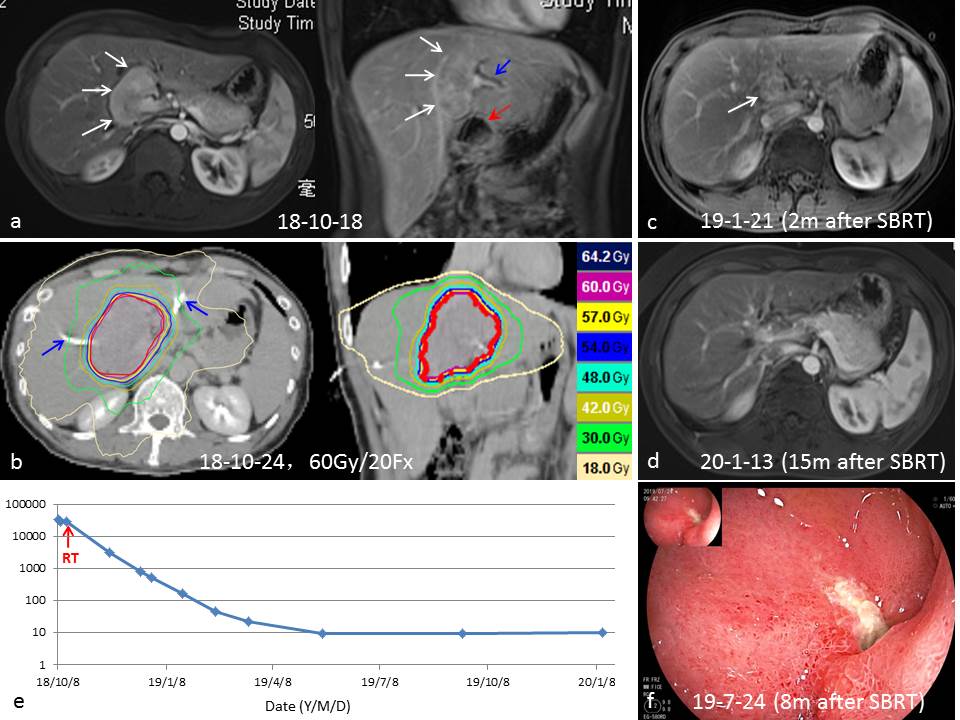

病例4

1、病例简介:

男性,29岁,以“皮肤黄染半个月”为主诉,诊断为肝门区HCC伴梗阻性黄疸,先外引流降黄疸。之后SBRT,3 Gy/次,共20次。由于十二指肠紧邻肿瘤下方(图a红色箭头)。 放疗结束后,患者总胆红素降至正常,肿瘤完全缓解,AFP降至正常。放疗结束9个月,患者诉腹胀不适,胃镜检查,十二指肠球降交界处可见一个溃疡(A1期),表面白苔,粘膜充血水肿(图f)。经过制酸治疗好转。

2、SBRT治疗过程中的影像学改变:

a. 横断切肝门区占位5.5 cm,动脉期增强;冠状切肝门区占位,静脉期强化减退,肿瘤下方紧邻十二指肠,红色箭头所指。

b. 放疗定位CT,可见左右胆管引流管(蓝色箭号),肝门区肿瘤放射剂量分布图,60 Gy/20 次。十二指肠紧邻肿瘤下方,受照射剂量50 Gy/20 Fx 15 ml, 55 Gy/20 Fx 10.6 ml, 60 Gy/20 Fx 2.4 ml。

c. 放疗后3个月随访MRI,肿瘤明显缩小(部分缓解),血供减少,拔除引流管

d. 放疗后15个月,肿瘤完全缓解。

e. 放疗前后AFP的变化,放疗半年,AFP降至正常水平。

f. 放疗后8个月,患者诉上腹部阵发疼痛,胃镜检查,十二指肠球降交界处可见一个溃疡,表面白苔,粘膜充血水肿,为放射性损伤。